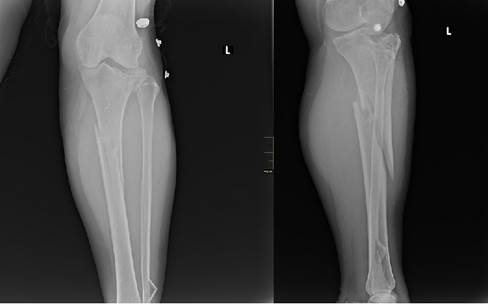

A la exploración física se detectó aumento de volumen desde la articulación de la rodilla hasta las uniones del tercio medio e inferior de la pierna izquierda. Además de lo anterior se constató movilidad anormal y crepitación a nivel del tercio medio de la pierna. Al tener en cuenta los antecedentes de la enferma de trauma y su presentación clínica se envió al departamento de imagenología, para realizar radiografías en vistas antero-posterior y lateral de la tibia afectada donde se observó solución de continuidad del tejido óseo a nivel de la meseta tibial externa tipo tres de Schatzker J, citada por Kuhn KM et al. 6 y tercio medio de la tibia de tipo oblicua larga y del peroné distal (Figura 1).